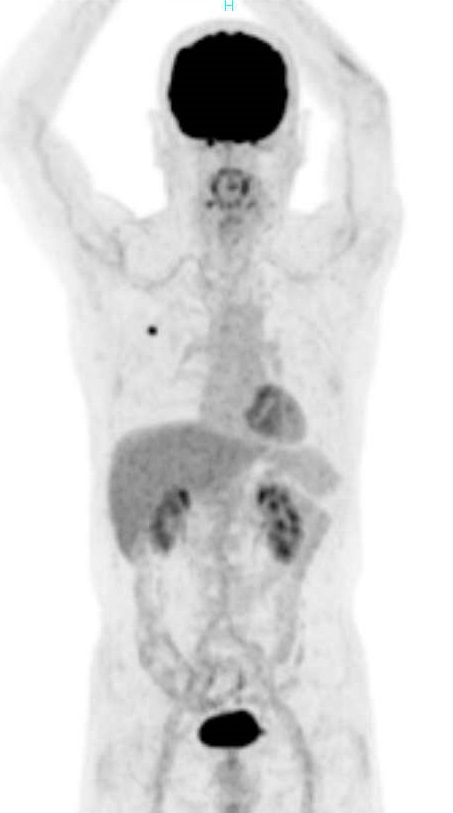

PET検査(右肺がん)